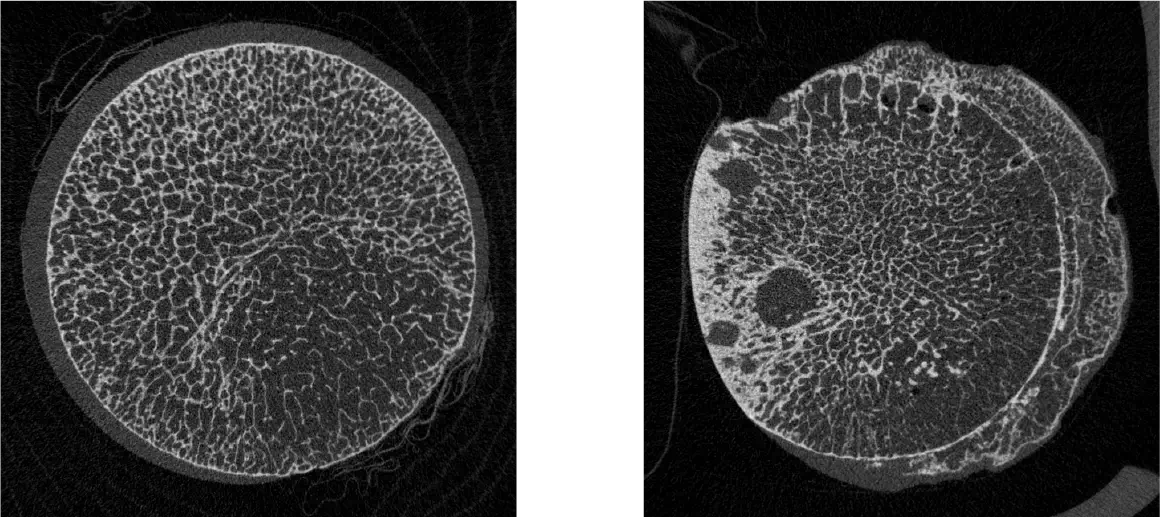

また、海綿骨だけでなく、皮質骨の微細構造を継時的に観察できるHR-pQCT(世界で約100台、日本では長崎大学に次ぐ2台目)が使用可能です。

HR-pQCT装置(高解像度の末梢骨用の定量的CT装置)

HR-pQCT(High-Resolution peripheral Quantitative Computed Tomography)は前腕や下腿の骨を高解像度で撮影し、骨の内部構造を三次元的に評価することができる最先端計測機器です。従来の骨密度検査(DEXA)では評価しきれなかった、「骨の質」や骨の細かい構造の変化を捉えることができ、より高度な骨粗鬆症の診断・治療効果の判定に役立ちます。HR-pQCTは研究機関や専門病院など、限られた施設でしか導入されておらず、先進的な骨の評価を受けられることが当院の強みのひとつです。大学や研究機関とも共同研究を行っています。実際に患者さまの骨の状態を詳しく評価し、テーラーメードの骨の治療を行うようにしています。

【撮影画像】

これらの装置を治療過程において効果的に用いることで、より効果的な医療を提供できると考えております。骨粗鬆症について、一緒に計画を立て「コツコツ」と治療をしていきましょう。